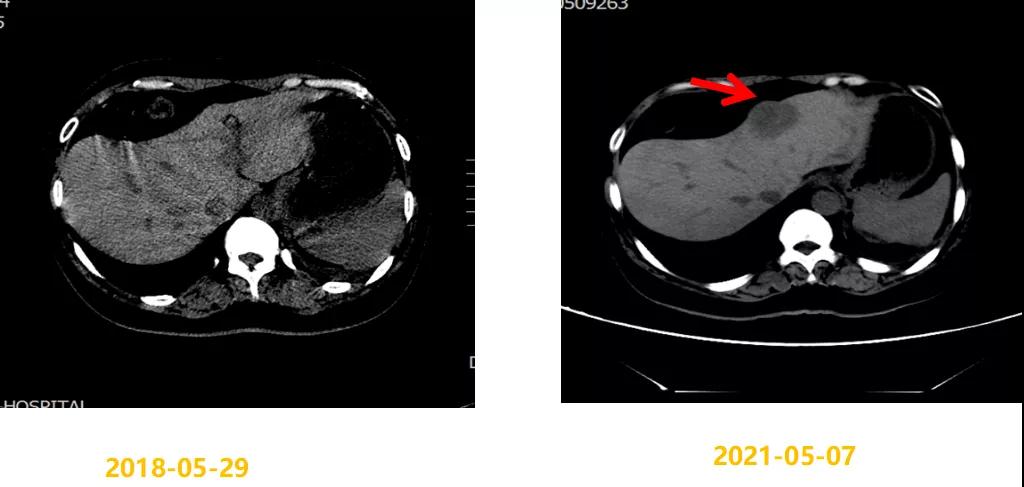

第二次病情进展:2021-05-07 CT示:左侧胸膜略增厚,同前相仿;肝脏稍低密度结节,考虑转移瘤,较前明显增大(大者4.4×3.7cm)。2021-05-08行“肝脏肿物穿刺活检”,病理结果:(肝肿物)符合转移性乳腺浸润性导管癌(组织学Ⅱ级)。免疫组化结果:ER(90%,3+),PR(85%,3+),HER2(1+),Ki-67(40%+)。

考虑患者既往辅助内分泌治疗敏感,一线内分泌治疗获益时间长,二线继续CDK4/6联合内分泌治疗,故2021-05-10起给予阿贝西利150mg po bid 联合阿那曲唑1mg po qd及戈舍瑞林3.6mg ih q4w,3月后疗效评估肝转移瘤较前稍缩小(SD),继续该方案治疗,至今PFS 6月,继续随访中。治疗期间Ⅰ-Ⅱ度骨髓抑制,对症治疗好转,无明显消化道反应,副反应较轻,可耐受。